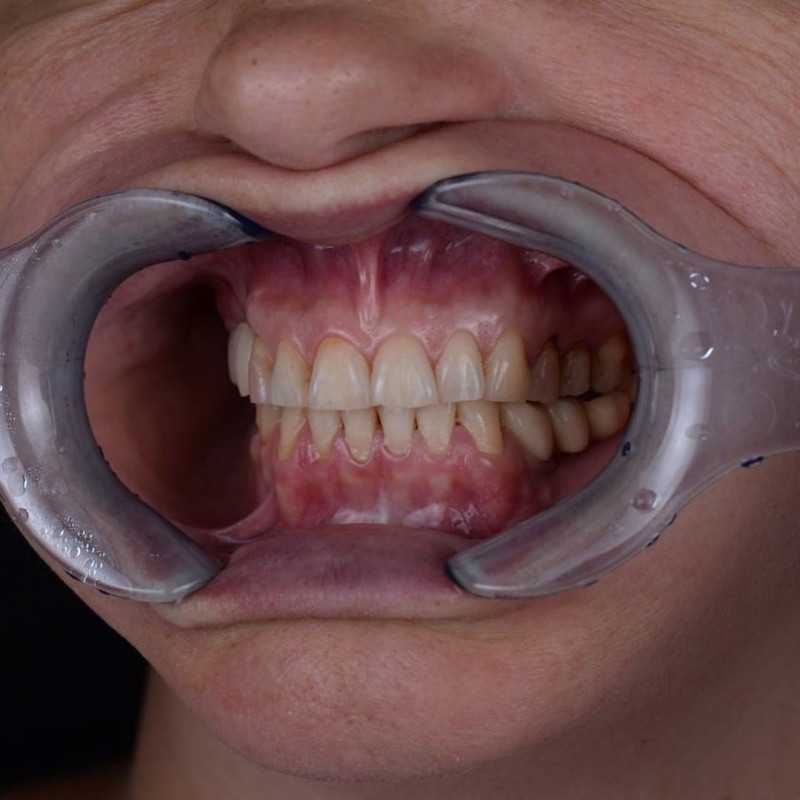

23 работы в портфолио

Главный врач Рамазанов Руслан Керимович принимает в Стоматологии NEW DENT (НЬЮ ДЕНТ) в Краснодаре. Имеет рабочий стаж 8 лет. Специализируется на ортопедии, по которой клиника оказывает 11 услуг. Имеет 23 работы до/после в портфолио. Квалификация специалиста подтверждена 19 лицензиями, сертификатами и наградами. Для уточнения дополнительной информации о специалисте или записи на прием можно позвонить по телефону